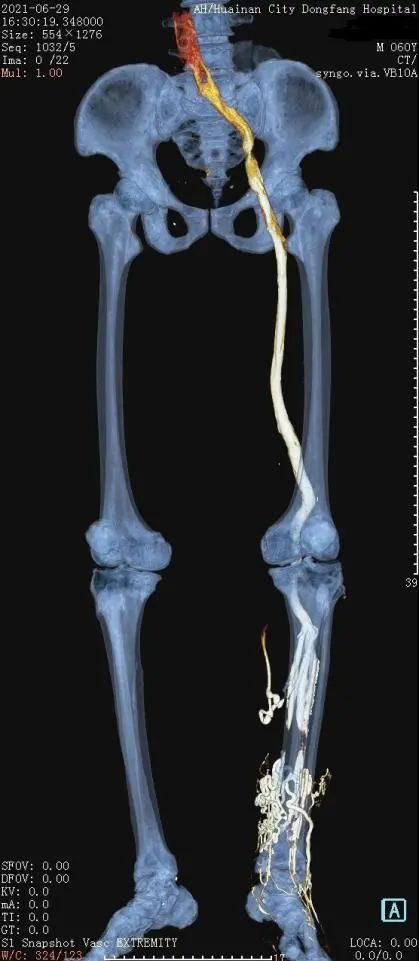

淮南东方医院集团影像中心和血管外科为了攻破此项技术,多次开展相关业务知识学习和培训,查阅大量前沿的文献资料,借鉴国内外成功检查经验,积极开展技术储备。近日,集团影像中心陈忠主任带领团队,在严格制定好技术参数、检查流程和应急预案的前提下,护理组、技术组、诊断组三个部门密切配合,在双源CT机器下完成三例下肢静脉CTA检查,检查过程顺利,图像质量满意,标志着该项技术已经正式应用于临床。

相较于以前的检查技术,螺旋CT下肢静脉造影检查技术(下肢静脉CTV)具备更多的优势:检查范围大,时间短,可以多角度显示下肢静脉血管病变的部位及范围,图像更为直观,而且具有微创、可重复等特点,扫描结束后利用数据进行二维和三维重建,观察血管腔内的病变情况,排查血管腔内有无血栓,术前评估下肢深浅静脉组的沟通情况,了解栓子形态及管腔狭窄情况,判断狭窄原因是腔内阻塞还是腔外压迫,还可以寻找血管损伤出血的部位,指导临床一线精准治疗。